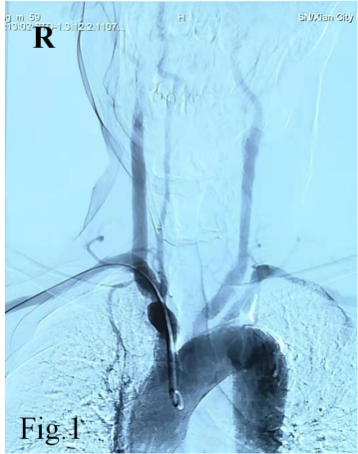

55岁的白先生因急性脑梗死入住成人导航 神经内科,双侧颈部血管、锁骨上窝均可闻及血管杂音,为详细评估脑血管情况,拟行全脑血管造影检查。常规的脑血管造影检查首选右侧股动脉穿刺入路完成造影,但是该患者存在明确的右下肢间歇性跛行病史,双侧股动脉搏动触摸不到。下肢动脉超声提示双侧股动脉中度狭窄,股动脉、腘动脉等下肢血管动脉粥样硬化斑块形成。仔细评估后,考虑无法从股动脉穿刺进行造影检查。经神经介入医生周密准备,拟进行经右侧桡动脉穿刺完成脑血管造影及下肢血管造影检查。

经过导丝引导下,谨慎地将造影导管置于主动脉弓,造影显示Ⅱ型主动脉弓,介入医生顿感压力倍增。常规路径下(股动脉置管),Ⅱ型主动脉弓要比Ⅰ型主动脉弓操作难度复杂的多,颈部血管从主动脉弓发出角度、走形、迂曲度及造影导管在主动脉弓如何塑形、塑形成功率等等都会制约操作时间、顺畅性,稍有不慎可能导致主动脉弓斑块脱落、主动脉动脉夹层等情况发生。增加了在经桡动脉在Ⅱ型主动脉弓上超选造影的难度。经介入医生耐心、细致操作下,反复尝试降主动脉造影导管成型,逐步“逆行”完成全脑血管造影及下肢动脉造影。